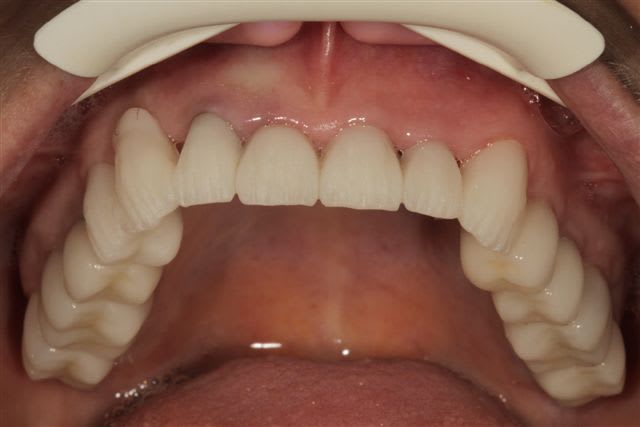

comme je l'ai dis plus haut le wax up ne parle pas à la patiente, j'ai donc au cours d'un rdv long, et à partir d'une empreinte du waxup, fait un "provisoire de présentation" en résine, sans fioriture juste pour que la dame comprenne mieux ce que je pouvais essayer de lui apporter.

On peut faire un montage sur photoshop mais ça n'a pas le même impact.

La patiente m'a demandé une fois le "maquillage" en place l'autorisation de le montrer à son mari...retour deux heures après, pas contente du tout ...que je dépose la résine.

et:" mon mari est d'accord pour refaire le haut mais le bas je ne peux pas"!

Et bien pas de bras pas de chocolat madame, pas de bas pas de haut...à plus tard.